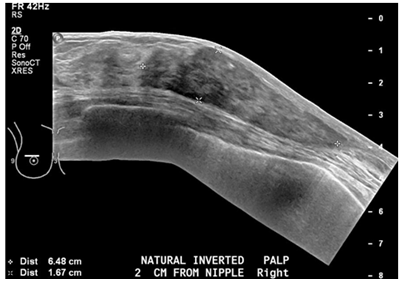

Diabetic mastopathy, also known as lymphocytic mastitis or lymphocytic mastopathy is seen occasionally in premenopausal women who have longstanding type 1 diabetes mellitus. This case underlines the importance of considering diabetic mastopathy on the list of differential diagnoses when evaluating breast lesions in a diabetic woman. Patients with DMP clinically present with painless, irregular hard unilateral or bilateral breast masses. It is rare as it represents represent 0.6% to 13% of benign lesions observed in woman with type 1 diabetes.2 Core biopsy is recommended for diagnostic confirmation. Pathology shows dense keloid-like fibrosis and periductal, lobular, or perivascular lymphocytic infiltration.3−5 The pathogenesis is not fully understood but many theories involving the effects of sustained hyperglycemia and glycosylated end products on the connective tissues of the breast have been proposed. Also it may represent an autoimmune reaction as the histologic features are similar to those seen in other autoimmune diseases.6 There are no large series with long-term follow up, but most reports recommend annual clinical and radiological monitoring and, in case of a new lesion, an additional biopsy must be considered. Once the diagnosis is established, excision is not necessary and malignant transformation has not been described. Conservative management is adequate for the majority of patients. Lesions have a tendency to recur after resection.2,7 Recognizing the presentation of this rare condition can help avoiding unnecessary surgical intervention (Figures 1 & 2).

Figure 1 Ultrasound of the breast showing Mastopathy changes, 311x222mm (72x72 DPI).

Figure 2 Ultrasound of the breast showing mastopathy changes, 321x218mm (72x72DPI).